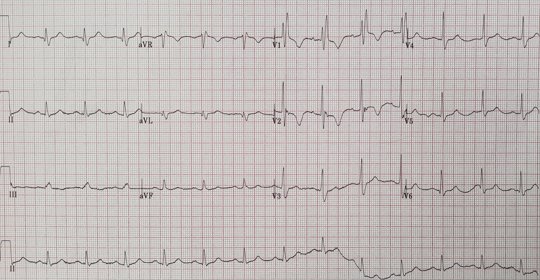

懷孕初期心電圖早搏

懷孕初期心電圖出現早搏的現象,可能是生理因素導致的,也有可能是病理因素引起。孕婦在孕早期時由於體內雌激素、黃體素水平變化較大,可刺激植物神經興奮性增加,從而影響到心臟功能,此時就會誘發早搏的情況發生。

懷孕心電圖異常怎麼辦

孕婦在懷孕期間進行心電圖檢查時出現異常的情況比較多見,如果僅是輕微的改變,並沒有造成心臟結構和功能傷害,則不需要特殊處理。但如果出現了嚴重的心律不整、心肌缺血等病變,則需要引起重視。

懷孕檢查心電圖

如果在孕期進行心電圖檢查提示正常結果,則無需擔心。但如果出現異常情況,如T波改變、ST段改變等,建議孕婦進一步完善相關檢查明確診斷,並遵醫囑治療。

懷孕心電圖異常的原因

孕婦在孕期進行心電圖檢查時出現異常,通常與生理性原因和病理性原因有關。其中生理性原因包括心臟體積增大、妊娠期高血壓、迷走神經興奮等,而病理性原因則可能為風溼性心髒病、先天性心臟病等。